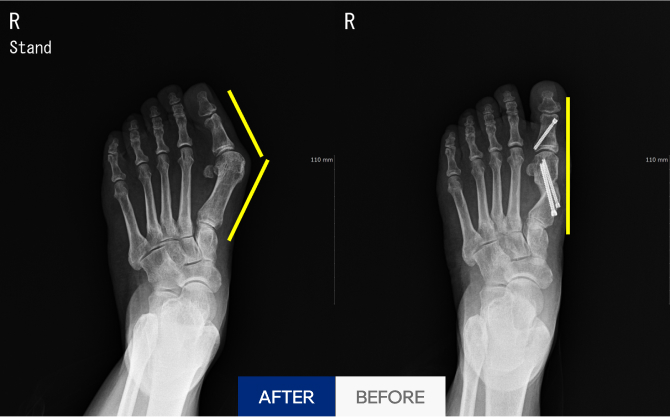

엄지발가락이 바깥쪽으로 휘고,

중족골이 안쪽으로 벌어지며 관절이 돌출되는 질환입니다.

단순 돌출이 아닌, 전체적인 발 구조 변형으로 이어질 수 있습니다. 초기 대응이 중요합니다.

수술전 정확한 진단 및 모양 분석

적은 흉터로 맞춤형 모양 교정